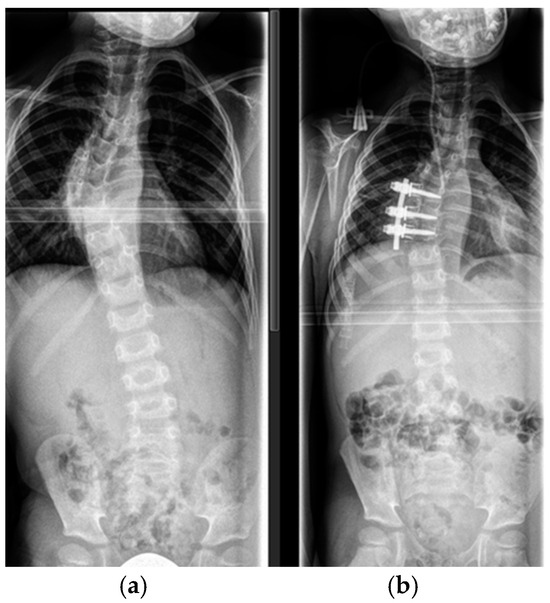

4.2.1. “Early Onset Spinal Deformity”

5.2.1. Growth-Preserving Techniques